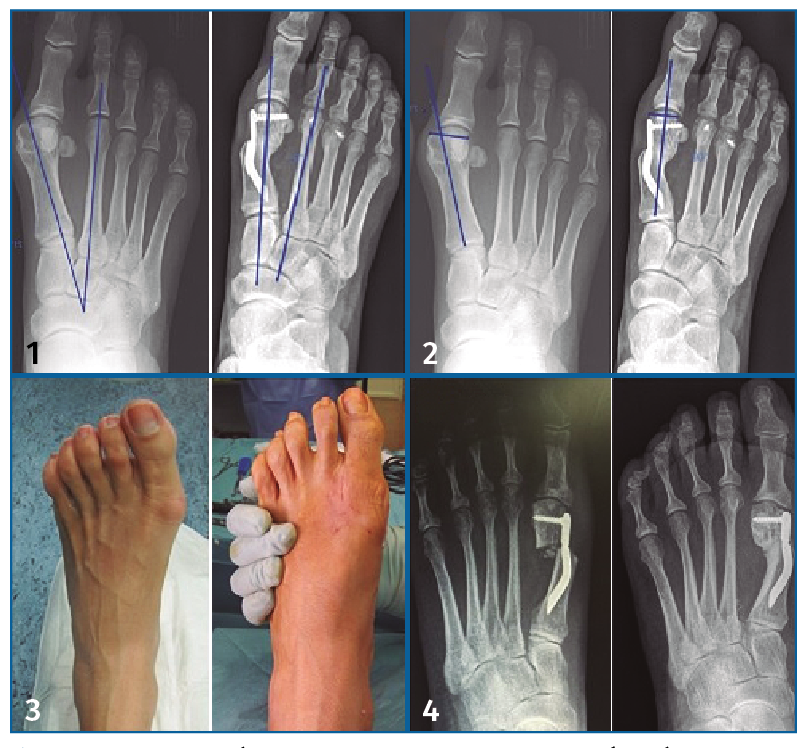

En todos los grupos se consiguió un alineamiento del ángulo IMTT por debajo de los 11°. Si analizamos la correlación entre el ángulo IMTT precirugía y la disminución absoluta de dicho ángulo, encontramos una correlación positiva de 0,61 (p < 0,005), lo que indica que existe correlación lineal positiva entre ambas variables, de tal modo que a medida que aumenta el ángulo IMTT, aumenta la disminución absoluta de dicho ángulo tras la cirugía. Si estratificamos la muestra en función de la severidad, encontramos que para las deformidades leves se consiguió una disminución media de 5°. No se pudo calcular el valor de p por insuficiente tamaño muestral en este el grupo. Para el HV severo se consiguió una disminución media de 11,67°, siendo un resultado estadísticamente significativo (Tabla 4). Podemos apreciar gráficamente la disminución del ángulo IMTT en cada caso clínico habiendo seleccionado los casos severos (Figura 3).

Figura 3. Disminución del ángulo intermetatarsal (IMTT) pre- y poscirugía en casos severos.

La consolidación radiográfica se obtuvo en el 82,9% de los pacientes (n: 29) a los 6 meses poscirugía y el 100% había mostrado consolidación a los 12 meses (Figura 5).

Figura 5. Resultados. 1: ángulo intermetatarsal pre- y poscirugía; 2: ángulo articular proximal pre- y poscirugía; 3: resultado visual de la deformidad pre- y poscirugía; 4: consolidación a los 3 meses.